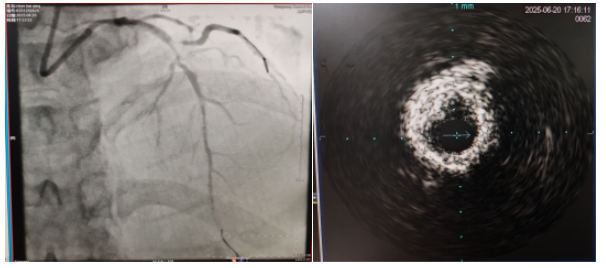

術(shù)中,趙慶禧主任醫(yī)師、雷剛副主任醫(yī)師運用IVUS血管內(nèi)超聲技術(shù)評估,發(fā)現(xiàn)患者前降支、對角支0.1.1型真性分叉病變,前降支近中段嚴(yán)重鈣化、成角并99%狹窄,對角支近段嚴(yán)重鈣化并99%狹窄,傳統(tǒng)冠狀動脈旋磨術(shù)容易引起冠狀動脈穿孔,決定采用沖擊波球囊技術(shù)即血管內(nèi)沖擊波鈣化碎裂術(shù)對患者嚴(yán)重鈣化的血管進(jìn)行介入治療。通過球囊低壓擴張,向血管病變處發(fā)射非聚焦、低能量、脈沖式的沖擊波,對前降支及對角支進(jìn)行了連續(xù)5個周期沖擊波脈沖治療,安全地碎裂淺、深層鈣化,原本看似堅不可摧的環(huán)形鈣化區(qū)逐漸顯現(xiàn)出了裂痕,多處關(guān)鍵位置發(fā)生了斷裂,充分預(yù)處理后于前降支近中段串聯(lián)植入支架3枚,對角支植入藥物球囊,術(shù)后造影見血管病變處狹窄完全消失,支架膨脹完全,貼壁良好,各項生命體征平穩(wěn),手術(shù)非常成功,患者返回心血管內(nèi)科病房繼續(xù)治療,并于4天后順利出院。